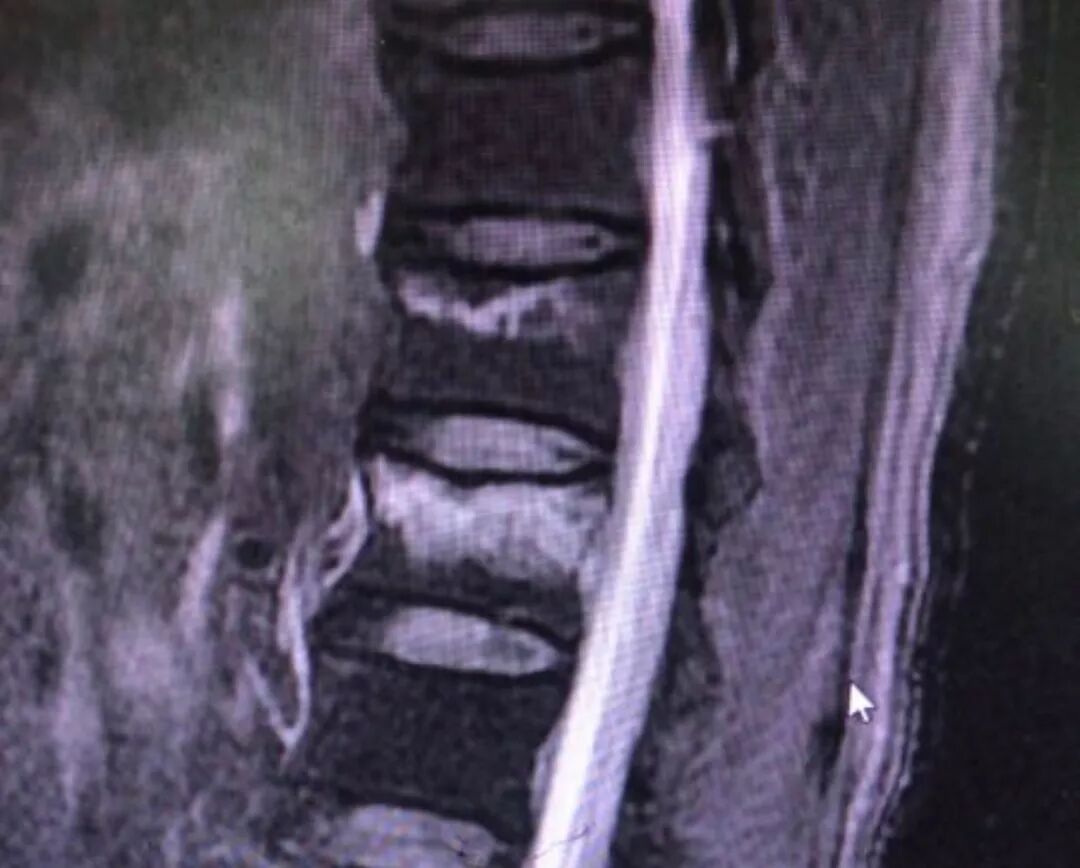

图片来自新浪博客

张大娘跌了一跤屁股坐到地上,当时也没有觉得身上有什么不适,除了屁股疼一点以外。张大娘慢慢走回家,还做了一点吃的,躺在床上休息。第二天发现起床的时候,腰部疼痛难忍,根本没有办法下地活动,躺在床上的时候,翻身也疼痛的厉害,只好到医院就诊。医院拍摄X-ray发现腰椎骨折。还好骨折并不厉害,卧床休息一个月就可以。